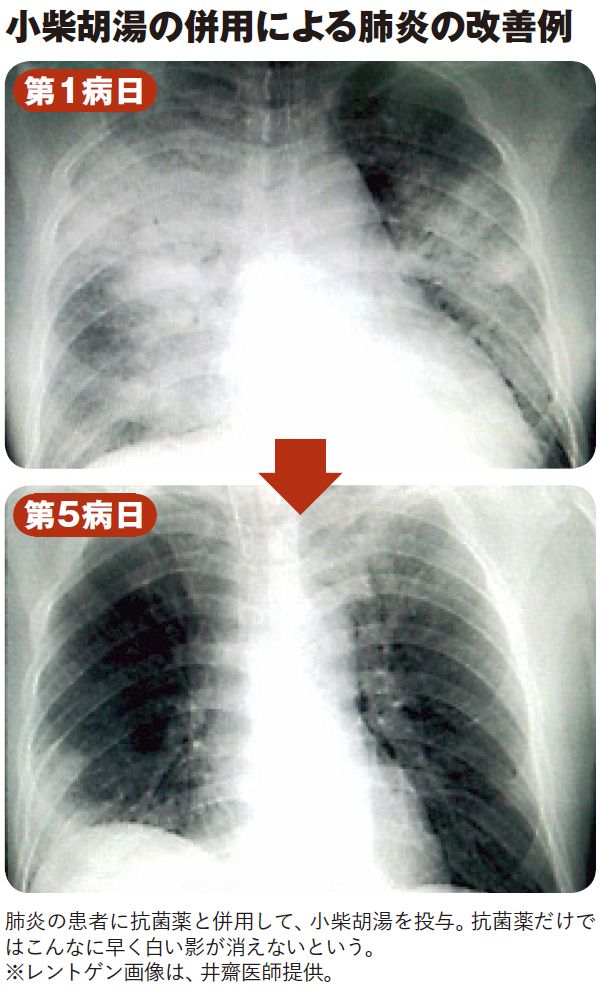

小林クリニック 症例集

なぜ 漢方薬安全神話 は崩壊してしまったのか あの有名な薬にはエビデンスがない 3ページ目 President Online プレジデントオンライン